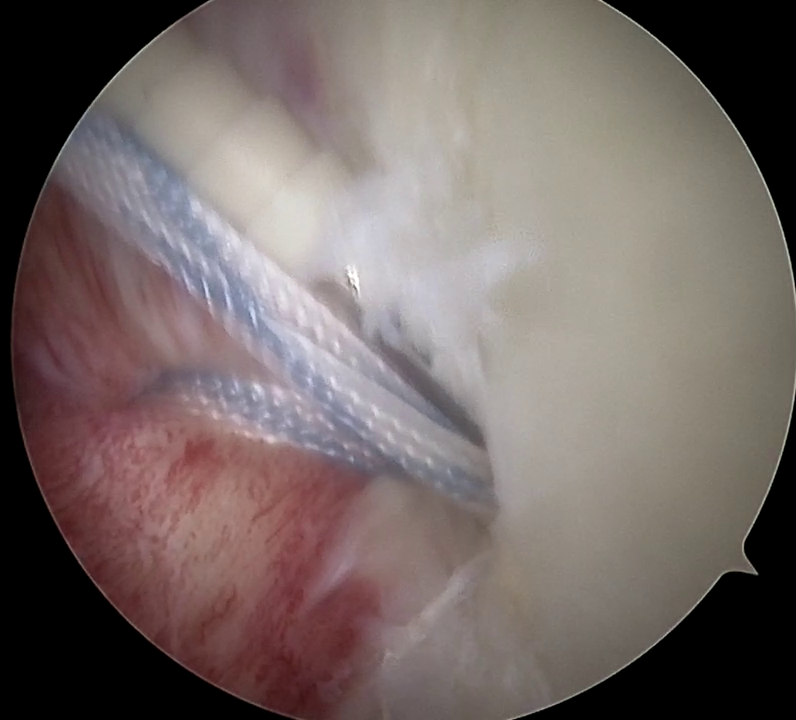

Αρθροσκοπική σταθεροποίηση Όταν η αστάθεια δεν μπορεί να αντιμετωπιστεί συντηρητικά, η αρθροσκοπική σταθεροποίηση αποτελεί την πιο αποτελεσματική λύση. Οι χειρουργικές επιλογές προσαρμόζονται στις ανάγκες του ασθενούς. Για πρόσθια αστάθεια με οστικό έλλειμμα ωμογλήνης μεγαλύτερο από 15%, ο Dr. Νικόλαος Πλάτων Σαχίνης εφαρμόζει αρθροσκοπική ανακατασκευή της ωμογλήνης με οστικό αυτομόσχευμα από το ιερολαγόνιο οστό του ασθενούς ή αναλόγως χρησιμοποιεί την τεχνική Latarjet λαμβάνοντας μόσχευμα από την κορακοειδή απόφυση του ώμου. Για μικρότερα οστικά ελλείμματα ή βλάβες τύπου Hill-Sachs, χρησιμοποιούνται συμπληρωματικές τεχνικές για σταθερό αποτέλεσμα.